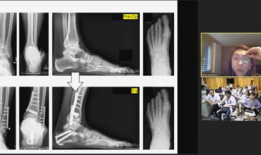

骨科视频,常见骨折与手术技巧全解析

亲爱的读者们,你是否曾因为关节疼痛而烦恼不已?又或者,你身边有没有朋友正在经历骨科疾病的困扰?今天,就让我带你走进一个全新的世界...

2025-11-17 88